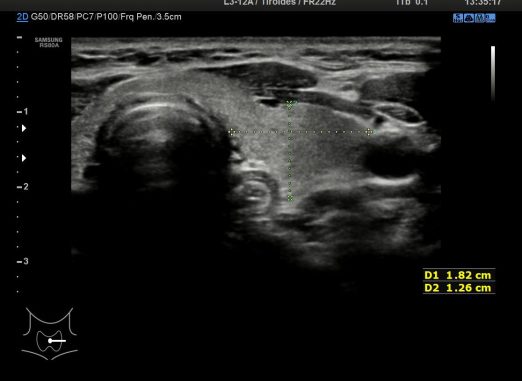

2. Medidas LD

Imagen 2 para las medidas AP y RL (Antero-Posterior y Derecha Izquierda) del Lóbulo tiroideo Derecho.Observamos dos vasos, Carótida Derecha y Yugular, interna y externa respectivamente.

Image 2 for the AP and RL measurements (Anteroposterior and Right Left) of the Right Thyroid Lobe. We observe two vessels, Right Carotid and Jugular, internal and external respectively